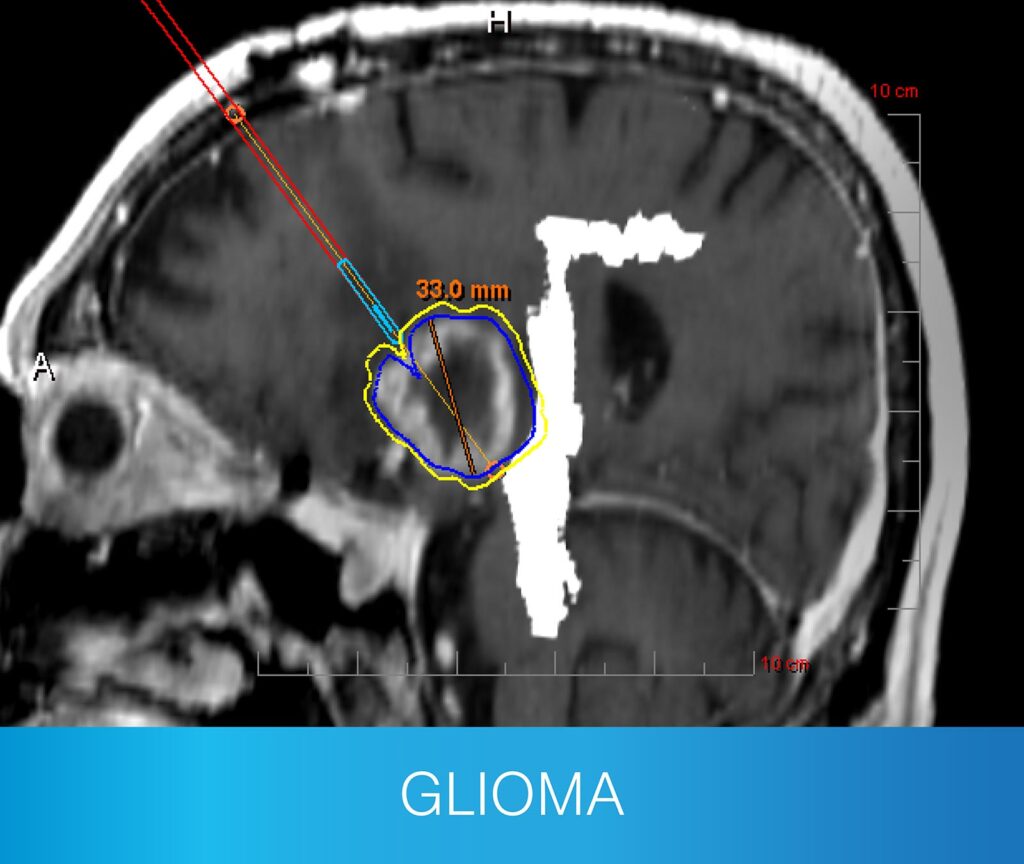

The NeuroBlate® System is the only minimally invasive surgical choice for robotic, cooled laser interstitial thermotherapy (LITT) that uses MR-guided surgical ablation technology designed specifically for use in the brain. NeuroBlate provides precise and maximal brain lesion ablation for adult and pediatric patients without the invasiveness of an open neurosurgical procedure.

Monteris continuously leads with surgeons’ preferred visualization platform: NeuroBlate® Fusion‑S™ Software — designed for safety and precision.

- Clear 3D Imaging: Shows detailed views of the brain and heat patterns during treatment to guide the procedure.

- Smart Scan Integration: Combines before-and-after images to plan and confirm ablation zones.